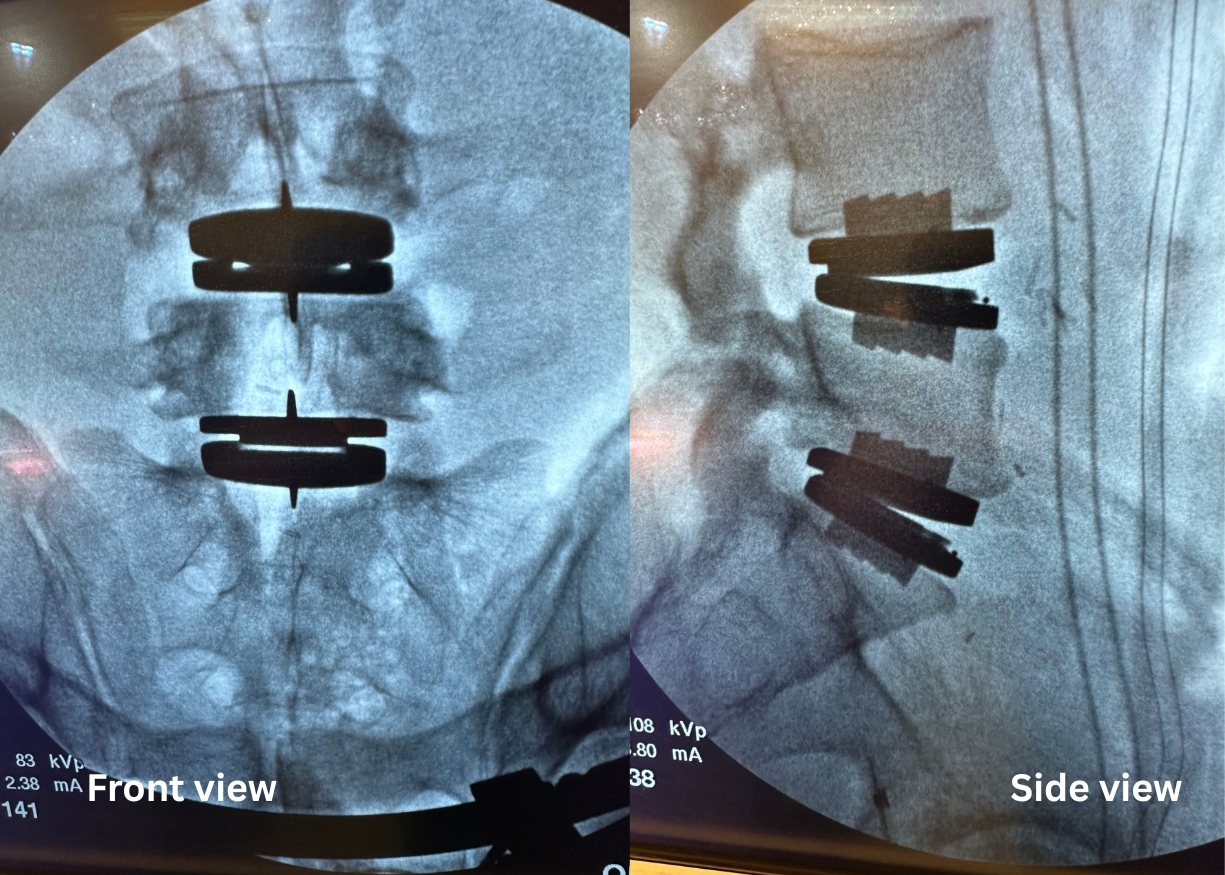

After

Lumbar disc replacement